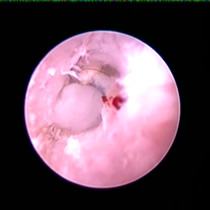

耳ダニ感染後の鼓膜喪失と中耳炎

長く耳ダニに気付かず治療が遅れた猫です。すでに鼓膜を失っており、中耳をきれいに洗浄すると赤い肉芽が確認できました。この肉芽を除去し点耳薬で治療すると改善。鼓膜が全く残っていないため鼓膜の再生は期待できませんが、痛みや痒みもなく元気に過ごしています。